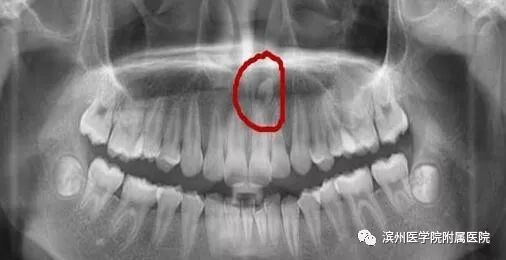

李奶奶的宝贝孙子6岁半了,上颌前面的两颗门牙已经替换了三个多月,可是两颗新牙间缝隙不见变小,反而越来越大了,远没有乳牙长得那么整齐。孙子门牙有大缝这事最近让李奶奶一直着急上火,平日总挂在脸上的笑容也不见了,今天一大早就带着孩子到滨州医学院附属医院儿童口腔科检查。儿童口腔科的医生经过专科查体并配合X线检查,发现是孩子的两颗新长门牙之间有一颗多生牙在作怪。

说说我的外形吧!普通牙齿都是左右对称的双胞胎,一点个性都没有,而我想长成什么样就长成什么样,大部分时候我都是酷酷的小火箭造型。有些时候,我会“装扮”成普通牙齿的模样混在它们中间,哈哈,让大家分不清哪个是我。

你问我长在哪?就生长的位置来说,那可就千变万化了。我不喜欢被约束,当普通牙齿都像小士兵一般整齐排队时,我却跑去探索骨内空间,偶尔插个小队,挡住去路不让门牙长出来,哈哈,想要从我这过,留下买路钱。我力大无比,谁阻挡我,我就推开谁。

看完这些,大家对多生牙有所了解了吧,正如上面所讲,如果是在替牙期,多生牙的位置会阻碍正常新牙的萌出通道,导致对应恒牙的萌出位置发生异常,例如牙齿发生扭转、倾斜、拥挤或牙缝过大甚至不能萌出。而且,多生牙奇怪的外形也会严重影响小主人口腔美观及心理健康;也有可能导致含牙囊肿的发生,若无视它继续生长,骨质逐渐向周围膨胀,则会形成面部畸形。